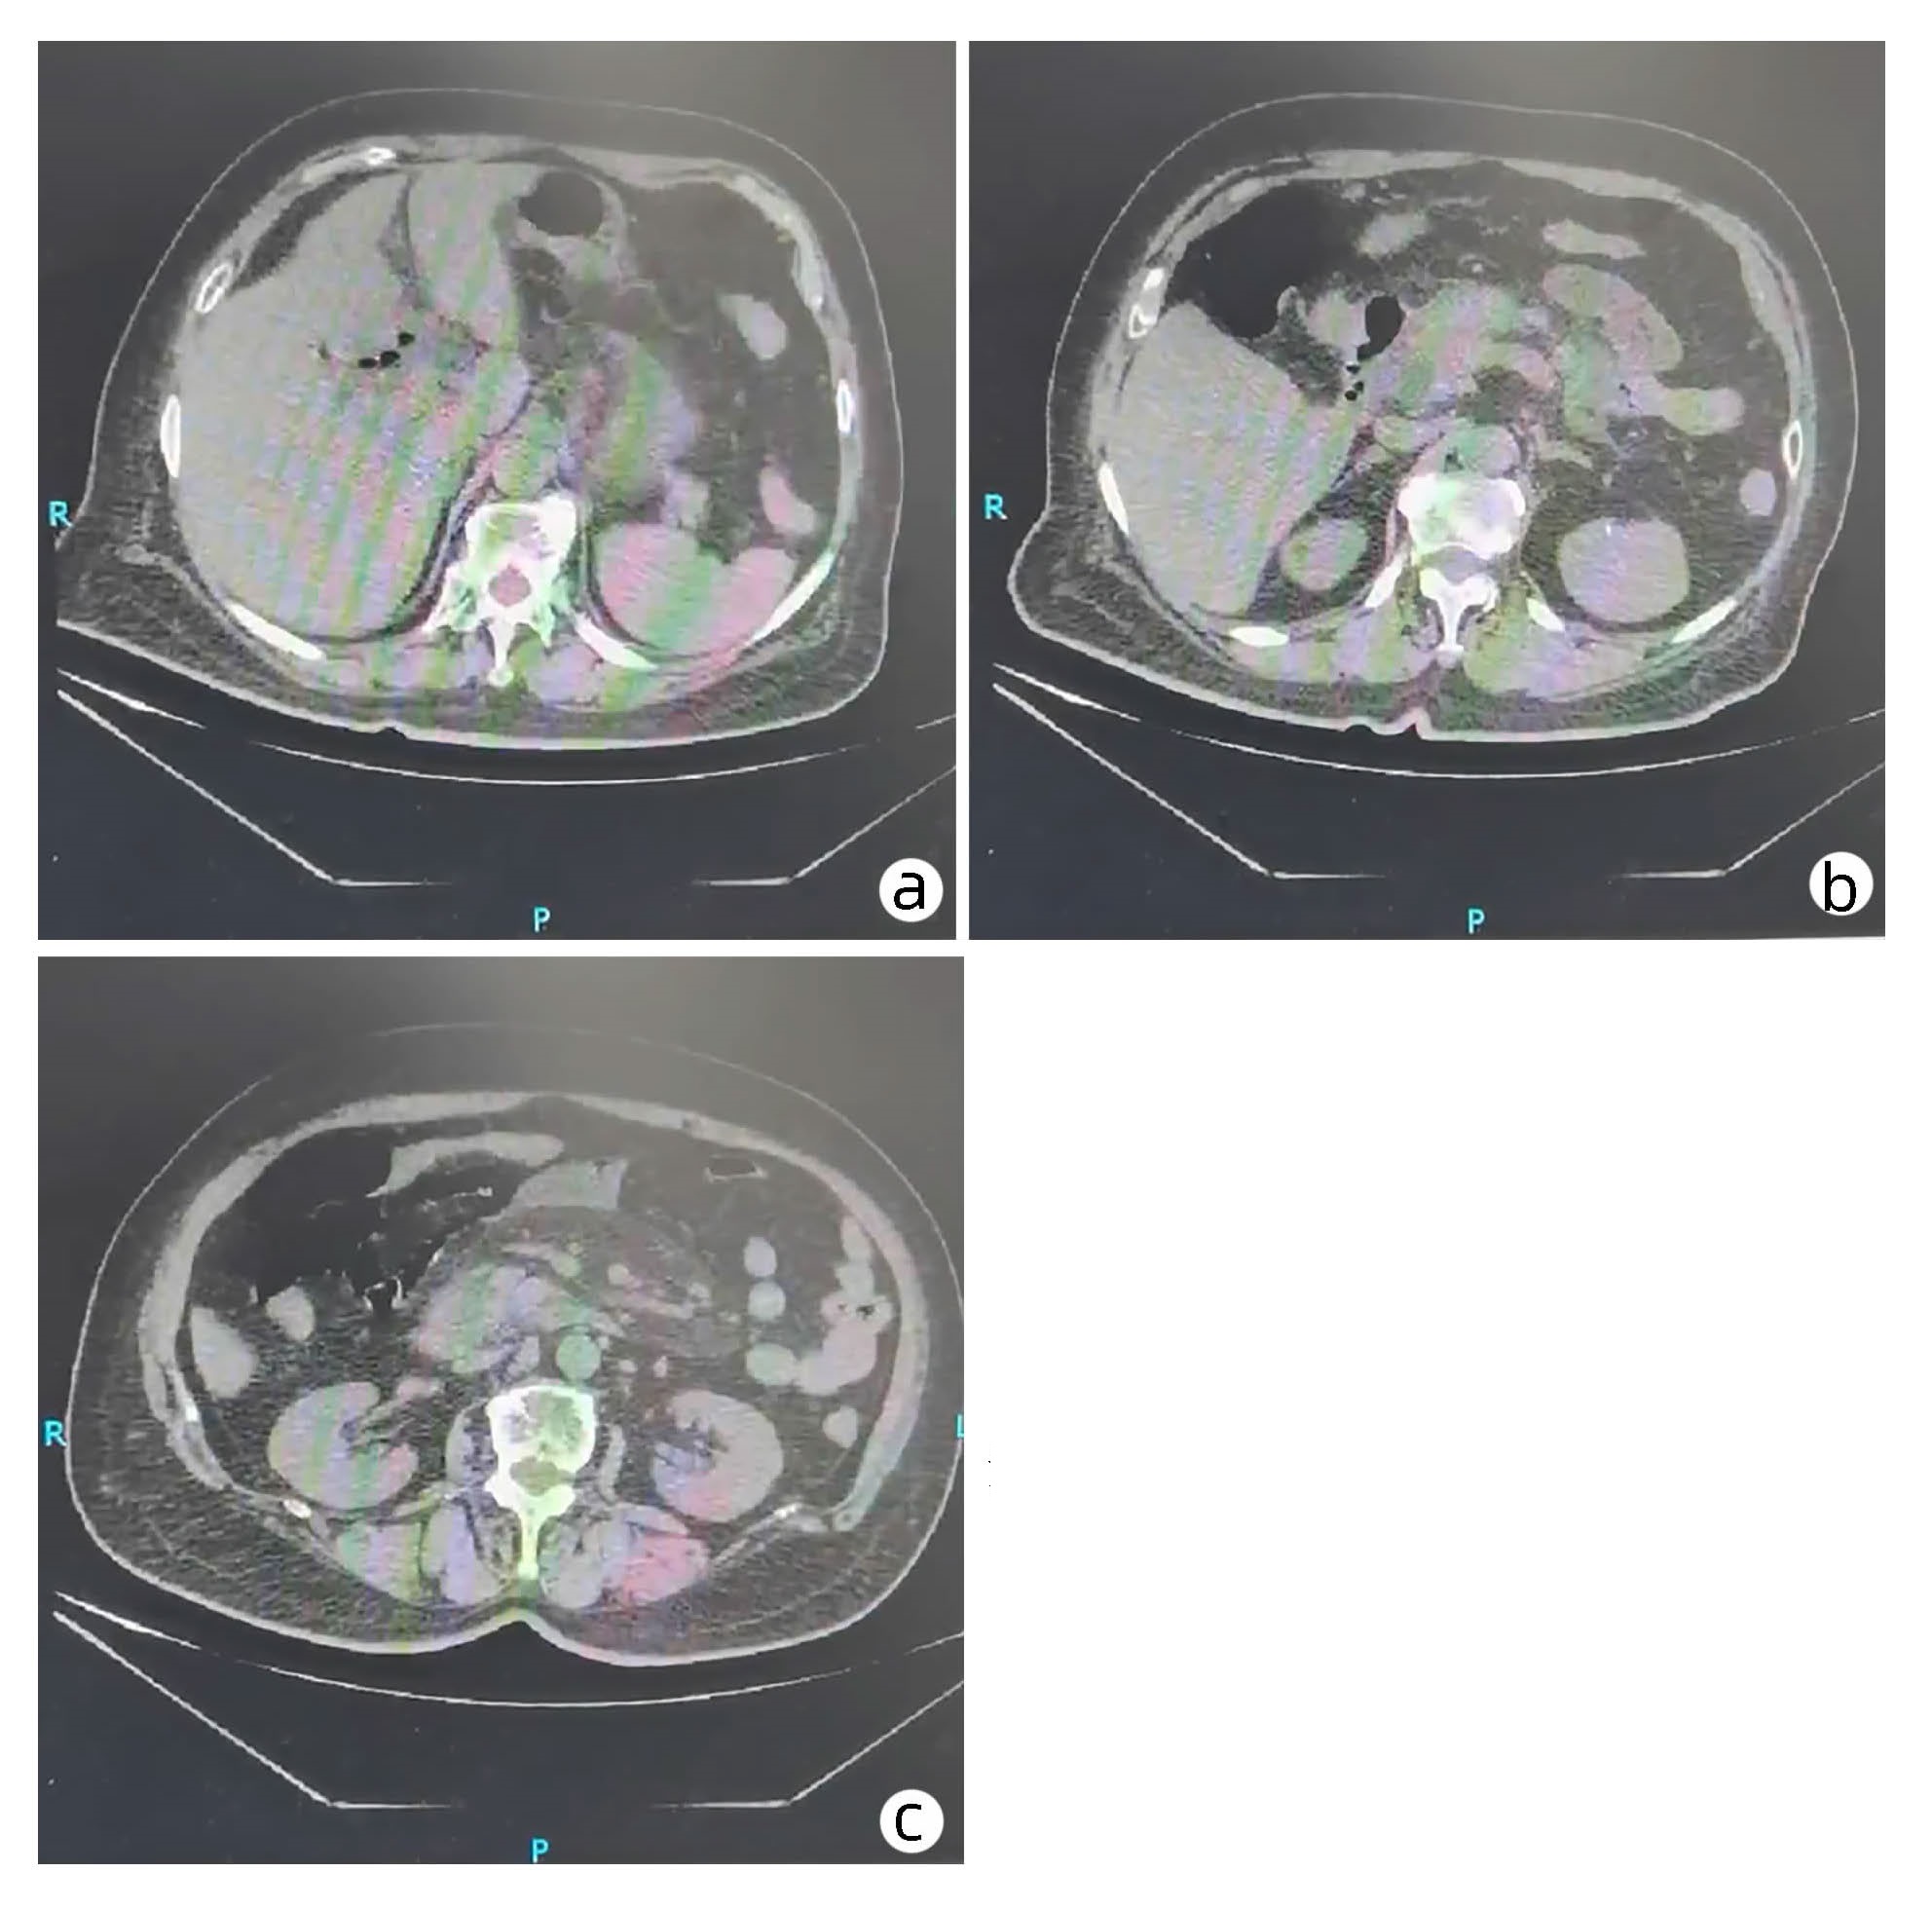

不典型肝血管瘤误诊为肝囊腺瘤1例报告

王莎, 张艳利, 陈圆圆, 马芹芹, 雷军强

2023, 39(5): 1154-1156. DOI: 10.3969/j.issn.1001-5256.2023.05.023

摘要(978) HTML (234) PDF (2557KB)(82)

摘要: